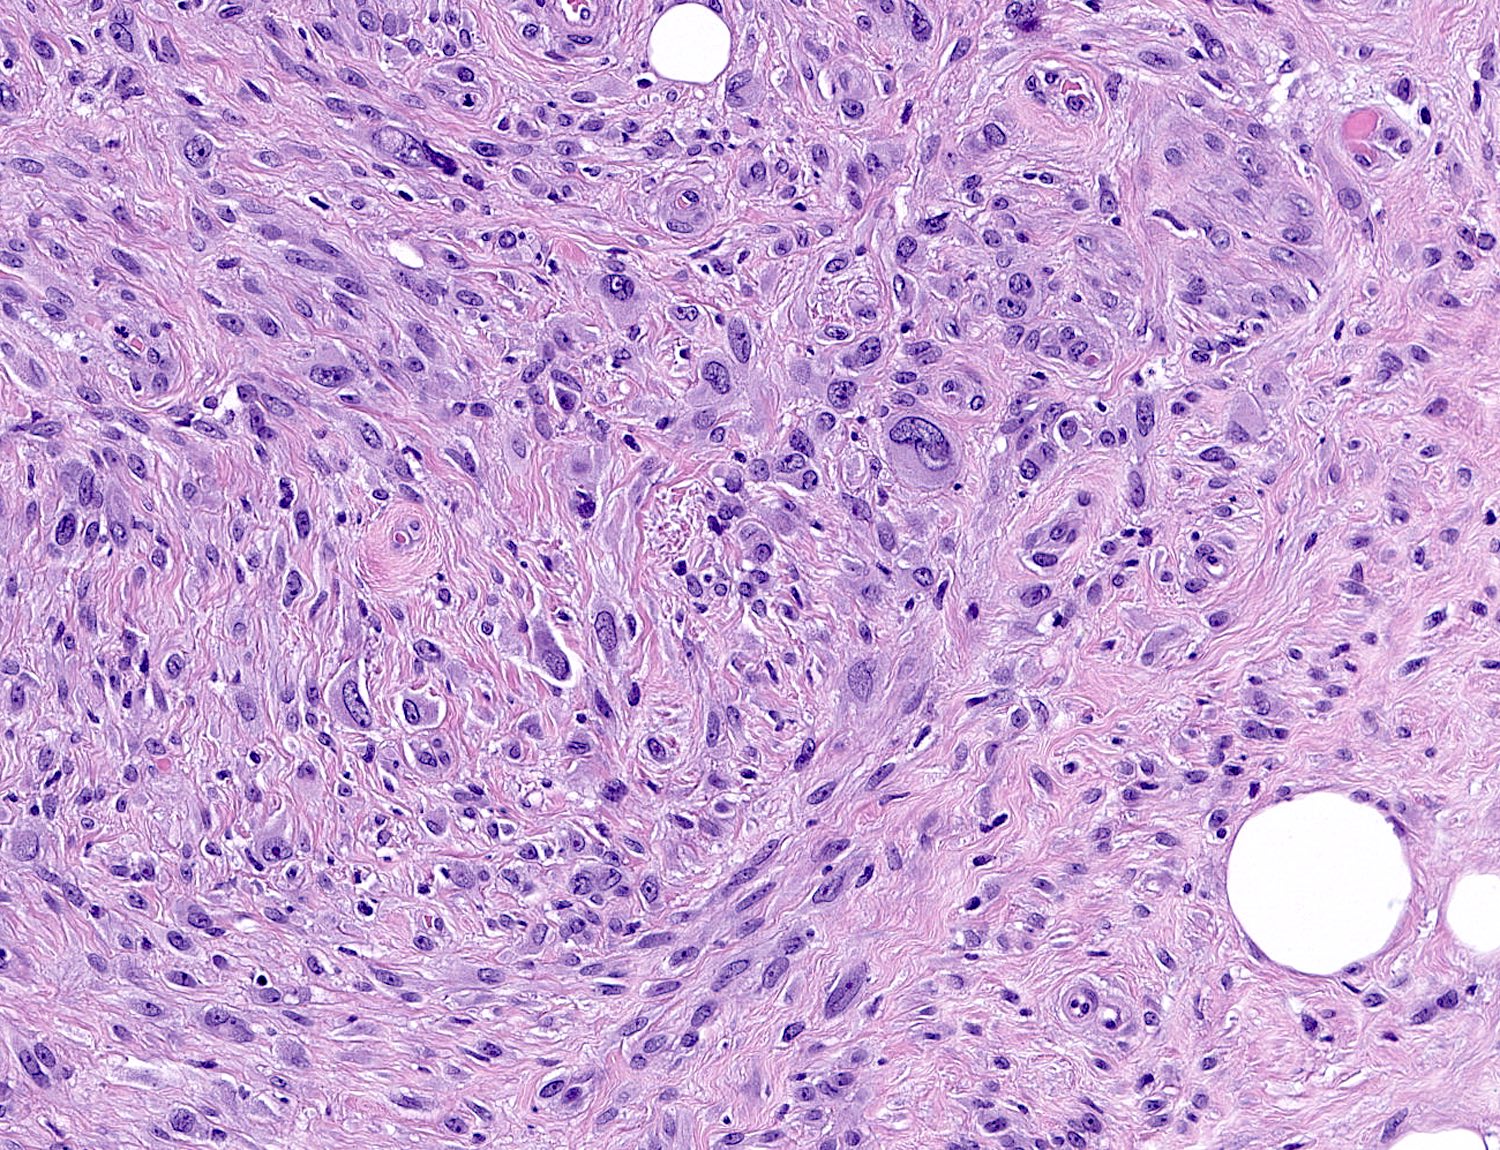

Microscopic (histologic) description

- Well circumscribed, lacks true capsule, rarely infiltrative

- Bland, uniform, short to elongated spindle cells arranged as short haphazard intersecting fascicles admixed with bands of hyalinized, brightly eosinophilic collagen and variable amounts of fat

- No more than mild nuclear atypia

- Mitoses usually absent, atypical mitoses and necrosis absent

- Mast cells common, perivascular lymphocytic infiltrates on occasion

- Focal myxoid stromal changes common

- Variants:

- Epithelioid: oval to polygonal cells arranged in clusters, cords, alveolar groups, linear strands, mono, bi or multinucleated, may have eccentrically placed nuclei with small nucleoli, well defined cell borders, single file arrangement may mimic invasive lobular carcinoma (Am J Surg Pathol 2009;33:1085)

- Atypical: single or scattered atypical mono or multinucleated cells with mild to severe nuclear pleomorphism, regarded as degenerative (Arch Pathol Lab Med 2008;132:1813)

Microscopic (histologic) images